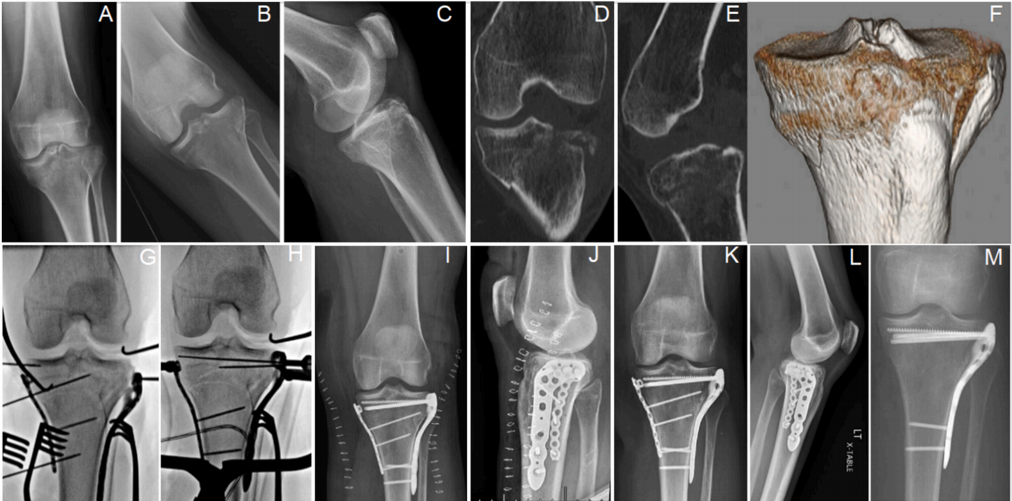

A-C) 62 岁男性劈裂塌陷型外侧平台骨折的 CT 扫描。 D-I) 术中 C 臂机 X 光片显示复位、关节骨块抬升和固定的步骤。 J, K) 术后 6 周随访 X 光片。 L, M) 术后 13 周随访 X 光片显示植入物稳定且骨折愈合。